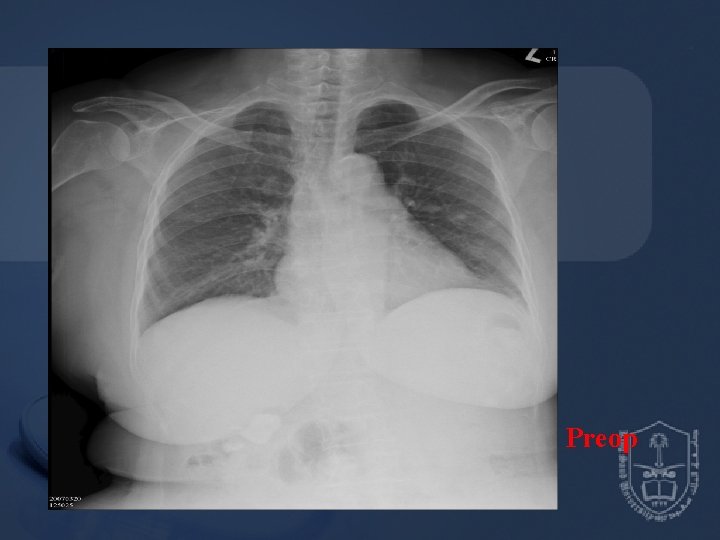

Pre-anesthetic Assessment • EKG : Normal sinus rhythm • CXR : Borderline cardiomegaly & tortuous aorta • Lab data : Hb 10. 5 / Hct 33. 2 BUN 24 / Creatinine 1. 1 GOT 14 PT, a. PTT WNL

Preop